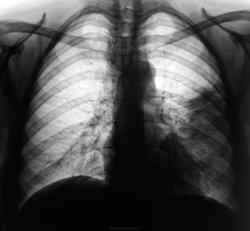

2-сегментарная верхнедолевая абсцедирующая левостороннняя пневмония, контроль после лечения. Возраст, клиника, анализы))

Откуда же 2-х сегментарная? Минимум S3,4,5, с рападом в S4 (полость покрупнее) и S3 (несколько мелких), частично дренированные. Явно выражен перициссурит с "сухим" плевритом.

Сегментов 3, но вот "уровни" как бы не вполне горизонтальные...

Нижняя доля несколько уменьшена…, не находите?